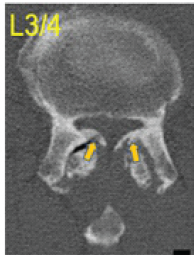

Pseudomeningocele Presenting with Neurological Symptoms 1 Year after Spinal Surgery: A Case Report

Shintaro Yamamoto , Ryunosuke Fukushi , Tomonori Morita , Arihiko Tsukamoto , Shutaro Fujimoto , Atsushi Teramoto

………………………………p.163-167